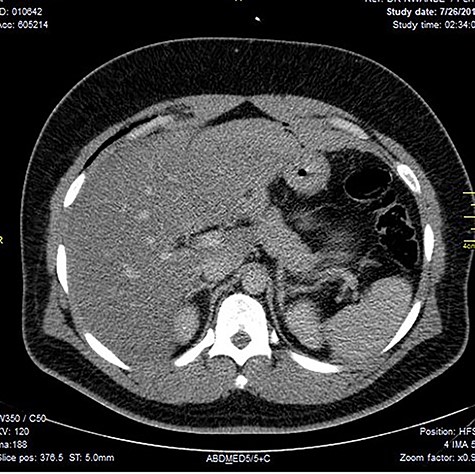

Chest X-ray was normal as shown in Fig. 1. Focused abdominal sonography for trauma (FAST) scan showed mild left perihepatic collection necessitating a thoracoabdominal computerized tomography (CT)-scan which showed external oblique muscle laceration with intermuscular air lucencies and grade 2 hepatic injury as shown in Figs 2–4. Other blood work-up were normal. No other injury was found on secondary survey. His wound was explored under local anaesthesia, primarily repaired, and he was discharged after 24 h of close observation.

Image shows lucent air densities tracking through the subcapsular haematoma in the left lobe of the liver anterior to the pylorus of the stomach.